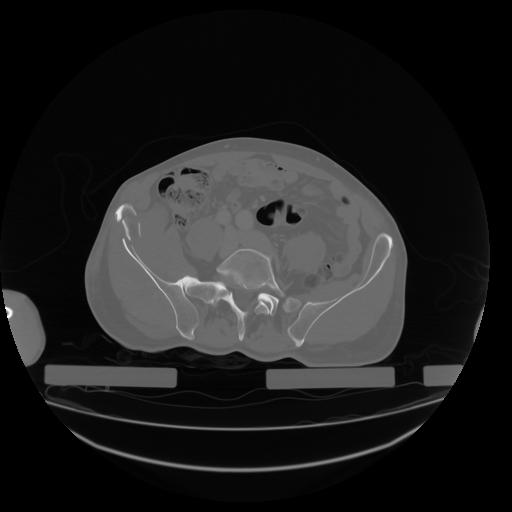

27 CUERPO,CE,Axial,3.0,CUERPO,,